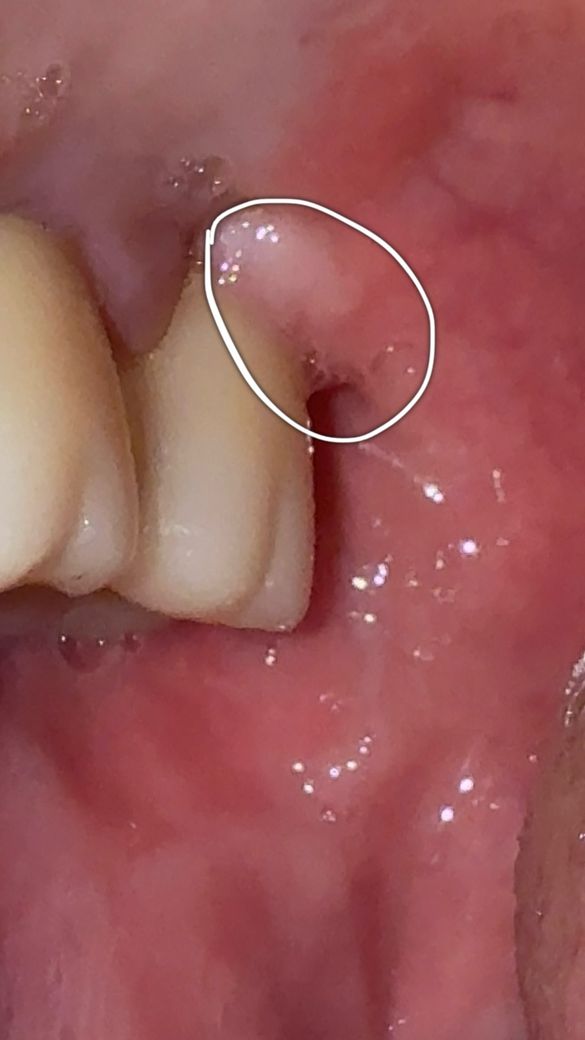

두번째 사진은 일요일에 점검 차 찍었던 사진입니다

• 2번 째 사진

임플란트 주위염이 생긴 것으로 보입니다. 저 정도 붓기이면 치과에 가서 검사 받고 치료 받아야 합니다. x-ray 찍어 임플란트 주위 잇몸뼈 상태도 확인해야 합니다.

염증이 있으면 그럴 수도 있습니다 치과가서 엑스레이 찍어보시고 필요하면 잇몸치료, 항생제 약 국소송달 해야합니다